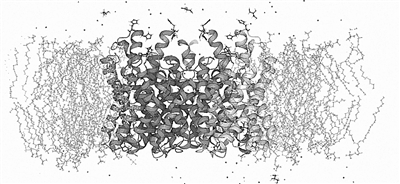

图为深势科技Hermite临床前计算机辅助药物设计平台界面